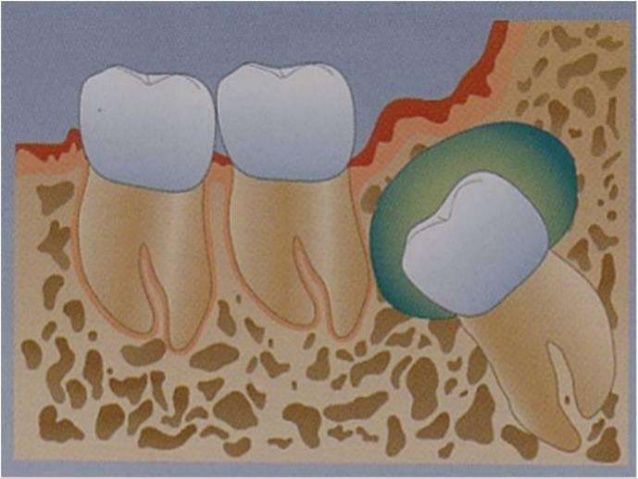

Definition: The dentigerous cyst is defined as a cyst that originates by the separation of the follicle from around the crown of an unerupted tooth.

The dentigerous cyst encloses the crown of an unerupted tooth and is attached to the tooth at the cementoenamel junction .

• The pathogenesis of this cyst is uncertain, but apparently it develops by accumulation of fluid between the reduced enamel epithelium (REE) and the tooth crown.

- The dental follicle may expand around the unerupted or impacted tooth in three variations : (a) circumferential (b) lateral (c) central or coronal